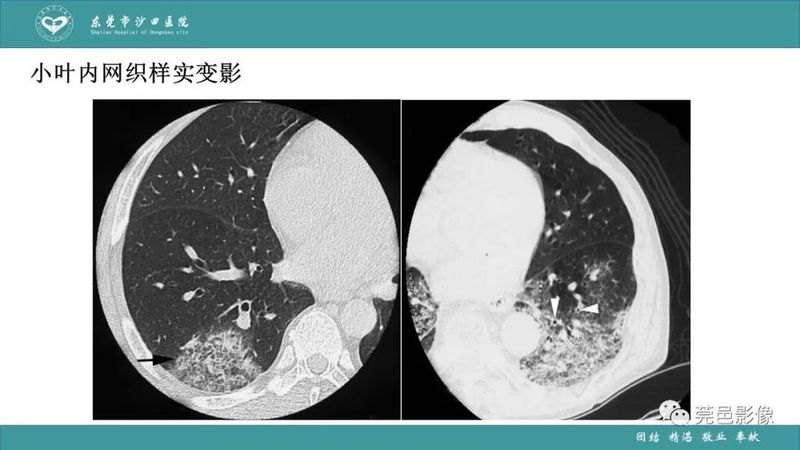

「肺炎克雷伯杆菌肺炎」影像学诊断+鉴别诊断